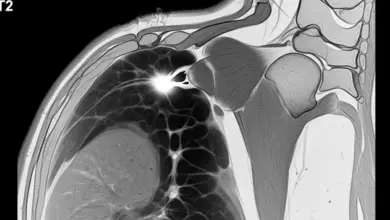

- Ressonância magnética ajuda a avaliar a cartilagem, osso subcondral e tendões, além de descartar outras causas de dor como lesões do manguito rotador ou conflito subacromial.